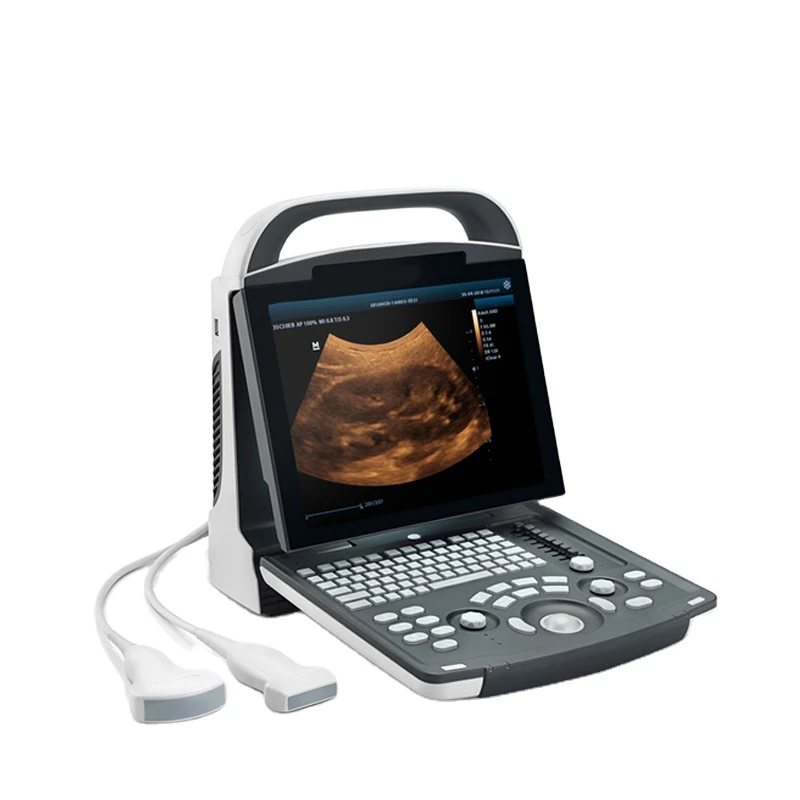

Portable Ultrasound Machine Mindray DP-10

12.1" LED Monitor

8-Segment

Light and compact

1 PCS

Abdomen, OB, GYN, Cardiology, Urology, Vascular

320Gb

Black and white